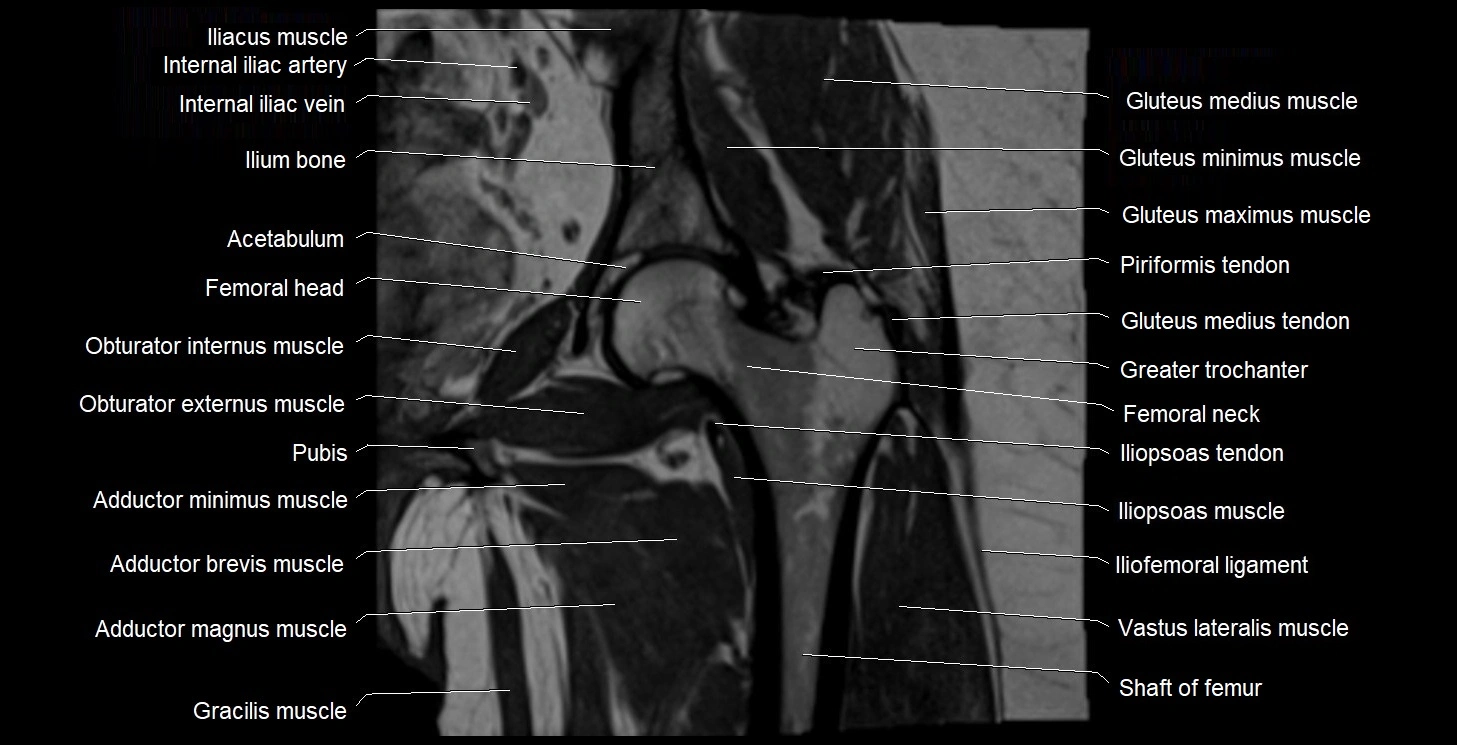

- Acetabulum

- Head of femur

- Ilium bone

- Iliopsoas muscle

- Iliopsoas tendon

- Iliofemoral ligament

- Internal iliac artery

- Obturator internus muscle

- Obturator externus muscle

- Gluteus medius muscle

- Gluteus minimus muscle

- Gluteus maximus muscle

- Gracilis muscle

- Greater trochanter

- Neck of femur

- Lesser trochanter

- Adductor magnus muscle

- Adductor minimus muscle

- Adductor brevis muscle